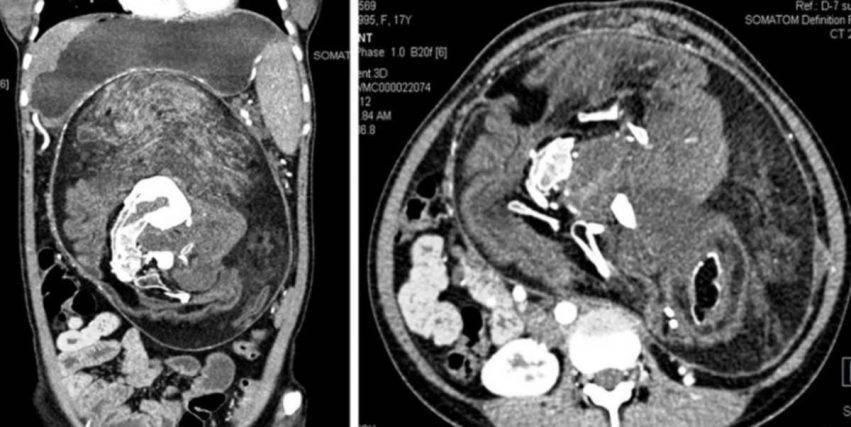

La paziente presentava un’escrescenza irregolare che le prendeva tutto l’addome.Una scan ha poi mostrato che la massa aveva aree di grasso, tessuto molle e diverse componenti di densità calcificate di varie dimensioni e forme che somigliavano a quelle delle vertebre, costole e ossa lunghe.

Così i chirurghi hanno rimosso la massa trovando capelli, ossa e altre parti del corpo.

La massa misurava 30x16x10 cm. ed era composta da capelli, diversi denti e arti pronti a sbocciare.